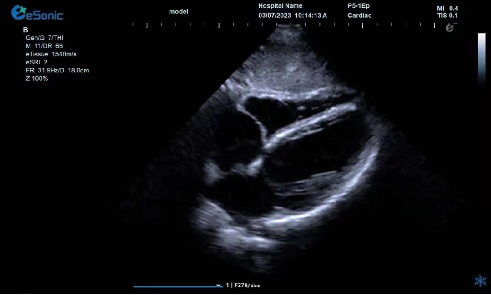

临床病例(一)

女性,68岁,临床诊断:冠心病

超声表现:左房大,左室壁运动幅度明显减低,以室间隔较明显;心包腔内见无回声区,右室前壁8mm,左室侧壁10mm。

冠心病、心包积液